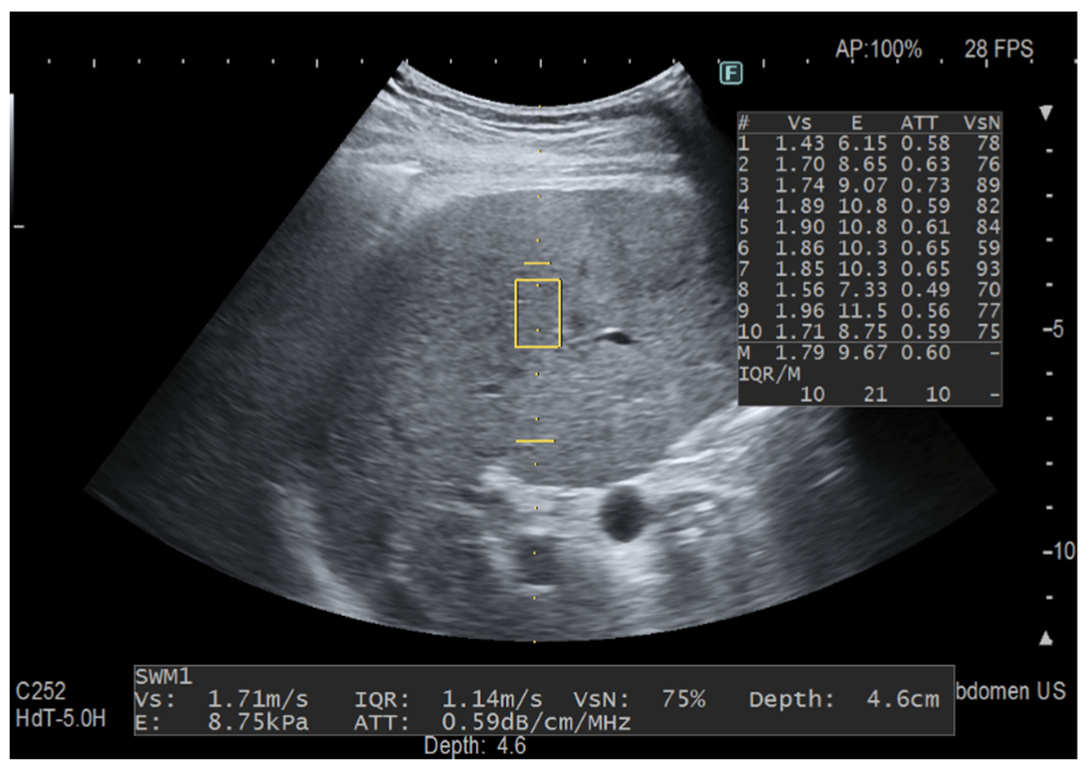

Figure 2.

Fat quantification with iATT. The two horizontal yellow lines graphically show the width (length of each line) and the length (distance between the two lines) of the iATT measurement area, which has a fixed size (length of 4 cm, from 35 to 75 mm from the skin). The measurement of the attenuation coefficient is given in dB/cm/MHz together with liver stiffness measurement. The yellow rectangle is the region of interest (ROI) for stiffness measurement. This measurement was taken in a 58-year-old patient with primary biliary cirrhosis but not steatosis.